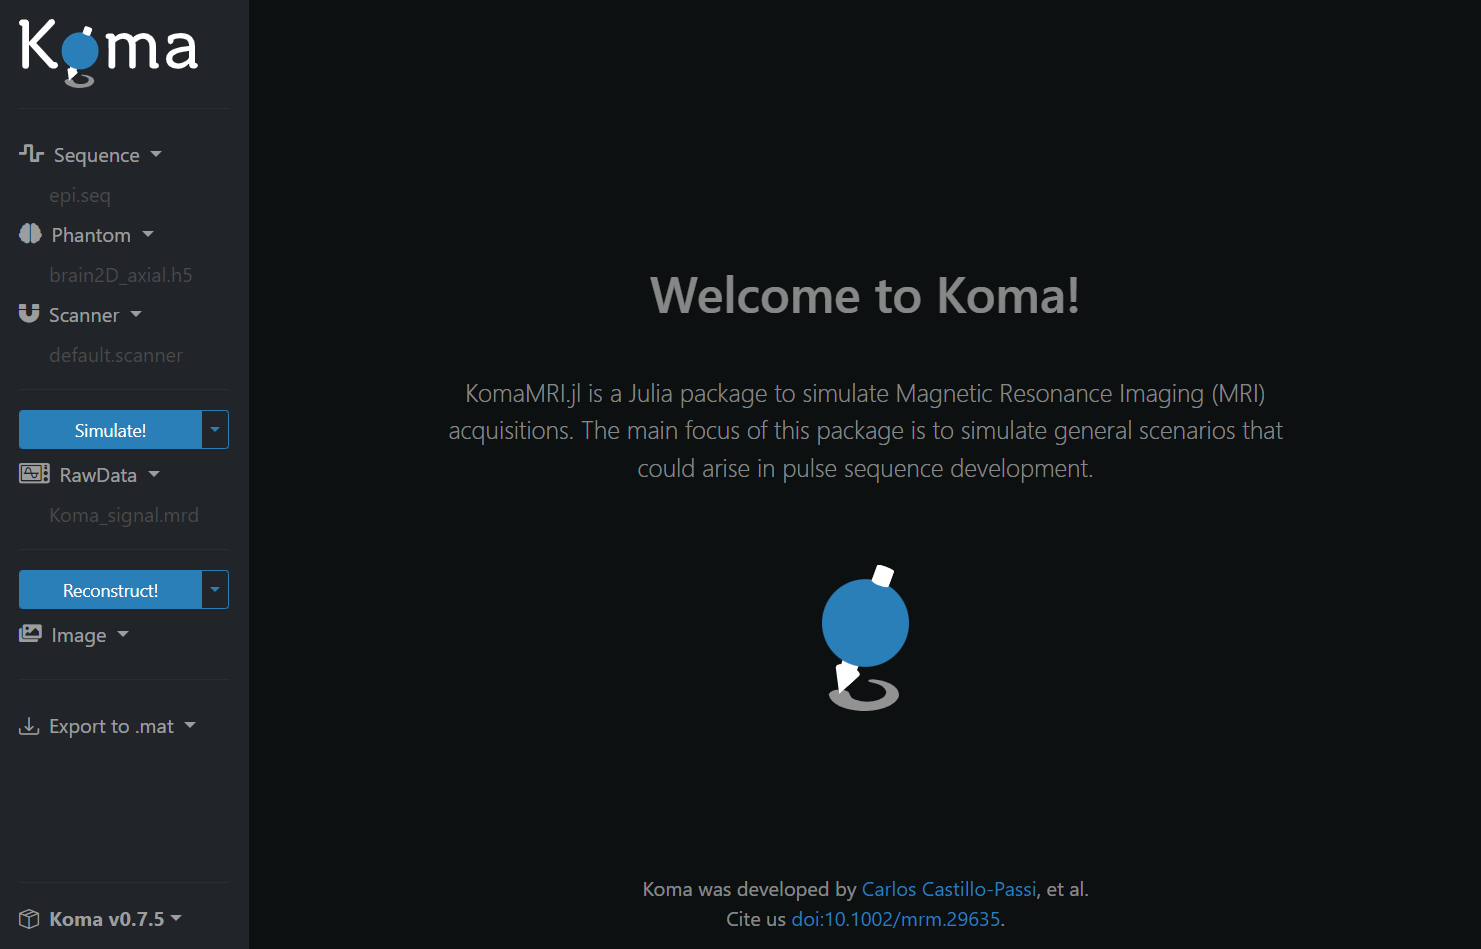

julia> KomaUI()The first time you use this command it may take more time than usual, but a window with the Koma GUI will pop up:

The user interface has some basic definitions for the scanner, phantom, and sequence already preloaded. So you can immediately interact with the simulation and reconstruction processes, and then visualize the results.